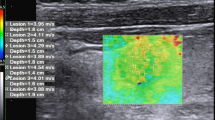

Whereas, the nodules that resulted malignant at histology had VTQ values with a mean of 3.751 ± 1.485 m/s, which was significantly higher than the value of benign nodules (2.141 ± 0.392 m/s; P < 0.001) and also higher than the value of the surrounding normal thyroid parenchyma (2.106 ± 0.491 m/s; P < 0.001). According to ROC curves (AUROC = 0.86 for Reader 1; 0.81 for Reader 2) sensitivity, and specificity for each reader were respectively 90 and 75 % for a cut-off value of shear wave of 2.455 m/s for Reader 1; 90 and 72 % for a cut-off value of shear wave of 2.365 m/s for Reader 2 (as shown in Figs. 1, 2; Table 1). The PPV and NPV for each reader were respectively 90.91 and 96.55 % for Reader 1; 90 and 95.90 % for Reader 2. Interobserver agreement was in the range considered good (k = 0.75). Intraobserver agreement was in the range considered good for benign nodules (k = 0.65 for more experienced reader and 0.63 for less experienced reader); and in the range considered good for malignant nodules (k = 0.65 for both readers). Figure 3 is an example of a benign nodule, and Fig. 4 of a malignant one.

Baseline US shows a non-well marginated, prevalently hypoechoic nodule (a) which at color-Doppler presented perilesional with some tiny intralesional vascular signs and at ARFI 2.59 and 3.19 m/s of shear wave velocity, respectively, for operator 1 (c) and operator 2 (d). At FNAC the lesion was classified as Thy 3; histological examination after thyroidectomy demonstrated that the nodule was a papillary carcinoma